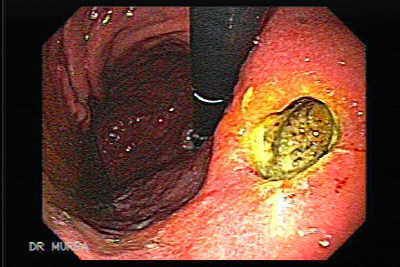

Si esta enfermedad no es trata a tiempo y de manera asertiva estamos expuestos a que ocurran complicaciones, podría ocurrir una inflamación prolongada del estómago y el esófago, lo que se conoce como esofagitis, la peor de todas las complicaciones, sin duda son las ulceras, el estrechamiento del esófago y en casos extremos, podría llegar a aparecer un cáncer.